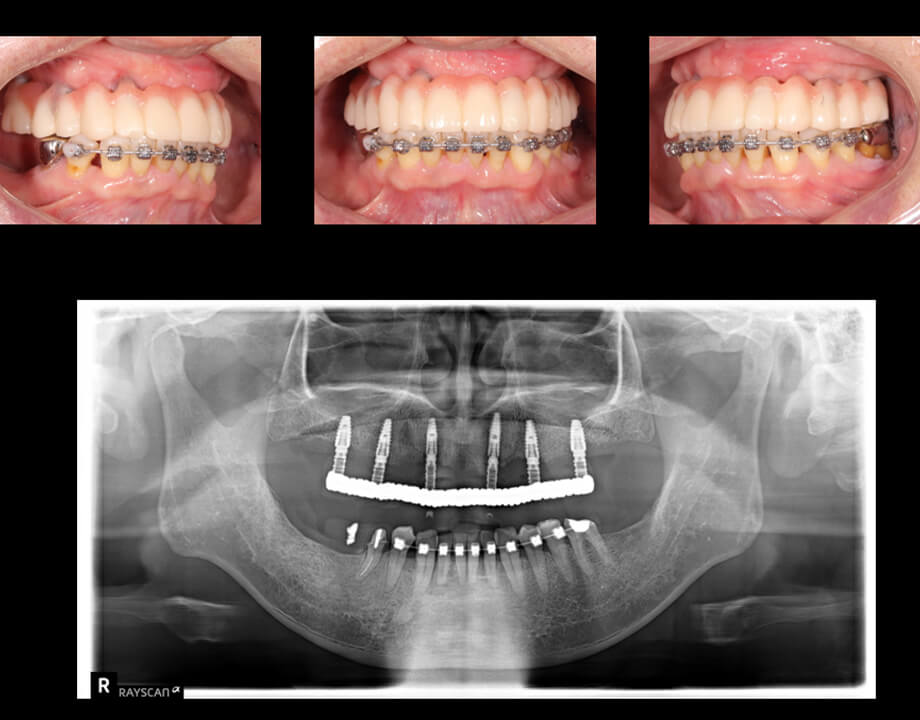

Case 06咬合再構成

デジタルワックスアップ

→シュミレーション(SMOP)

→プロビジョナル

→最終補綴物(モノリシックジルコニアAGC)